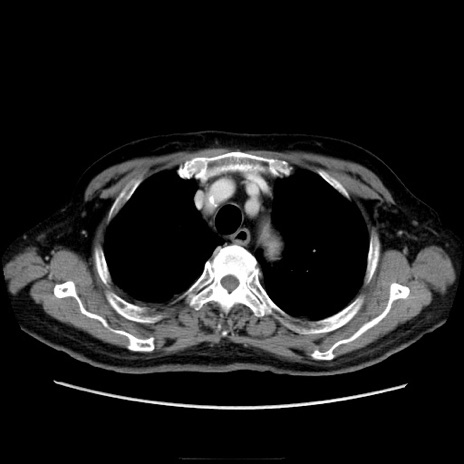

冠状断像

【症例】70歳代男性

【現病歴】肝硬変・肝細胞癌にてかかりつけの方。約9時間前に食後より腹痛出現。症状が徐々に増悪し、嘔吐出現したため来院。

【既往歴】肝硬変、肝細胞癌(RFA、TACE後)